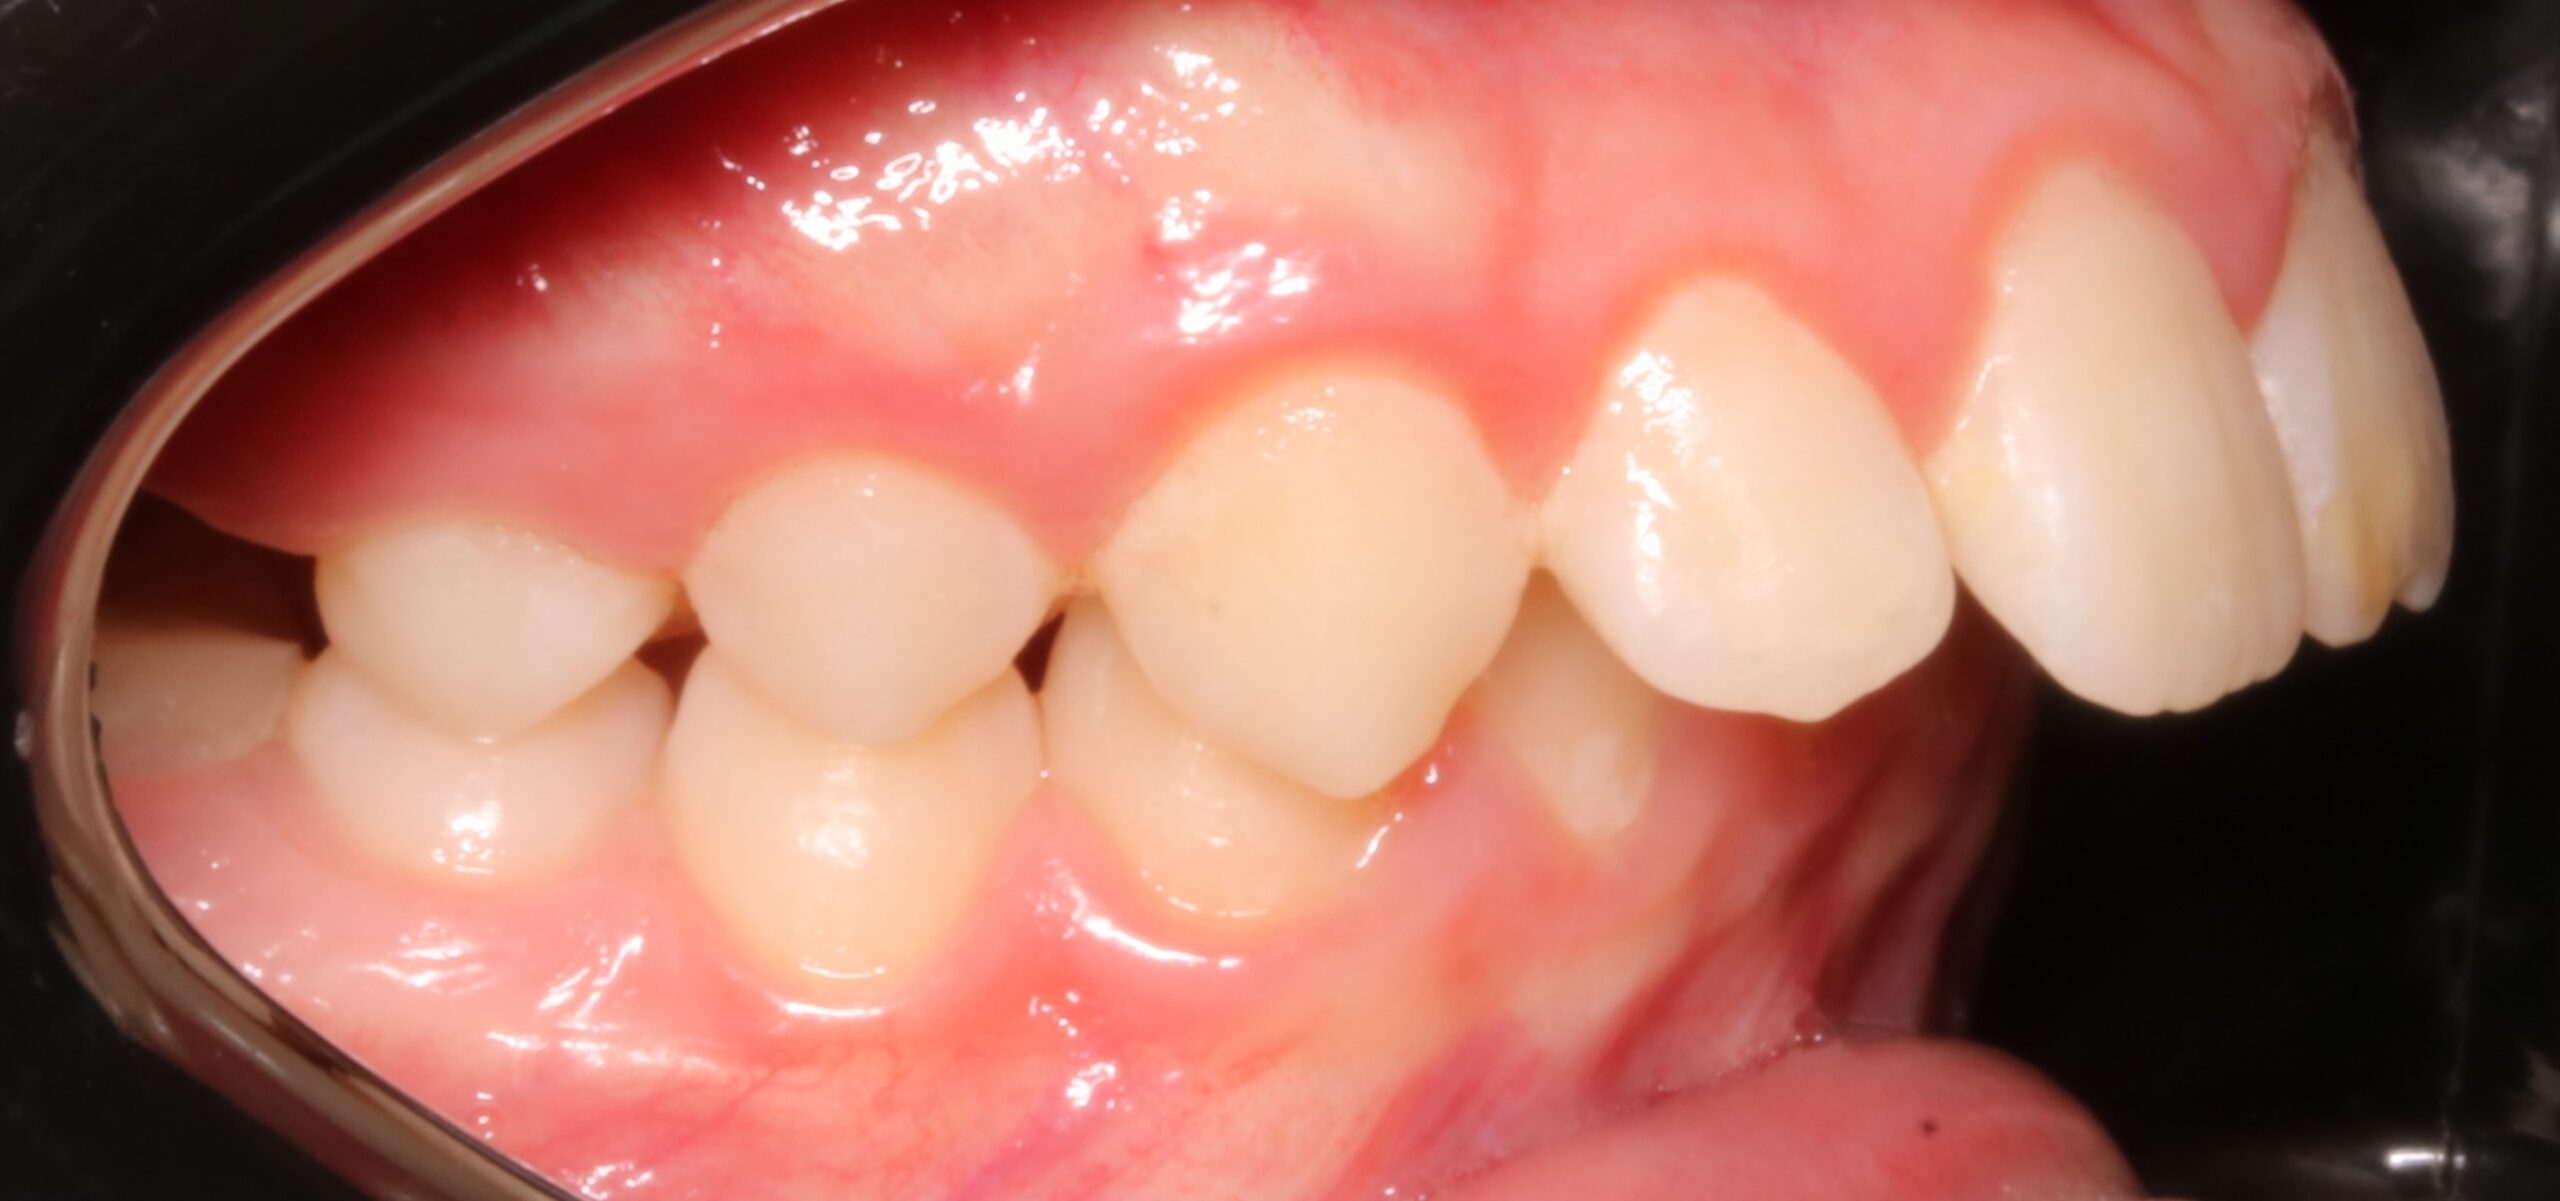

CLASE II MOLAR Y CANINA BILATERAL CON PERFIL DE MANDÍBULA RETRUSIVA AVANCE MANDIBULAR (CAMBIOS A NIVEL FACIAL+ CLASE I MOLAR Y CANINA)